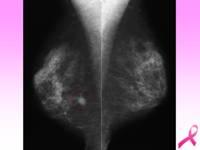

マンモグラフィで見た病巣

中央の黒い不整な乳腺組織を発見